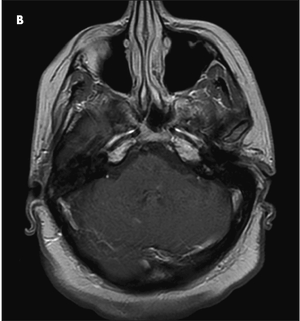

For a month, an obese 50-year-old woman with type 2 diabetes mellitus, hypercholesterolemia, and hypertension had blurry vision in both eyes. During this time, she also had ataxia and right-sided numbness. For the past 2 days, she had had horizontal, binocular diplopia with right gaze.